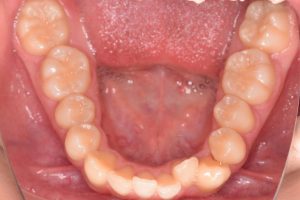

下から

下あご